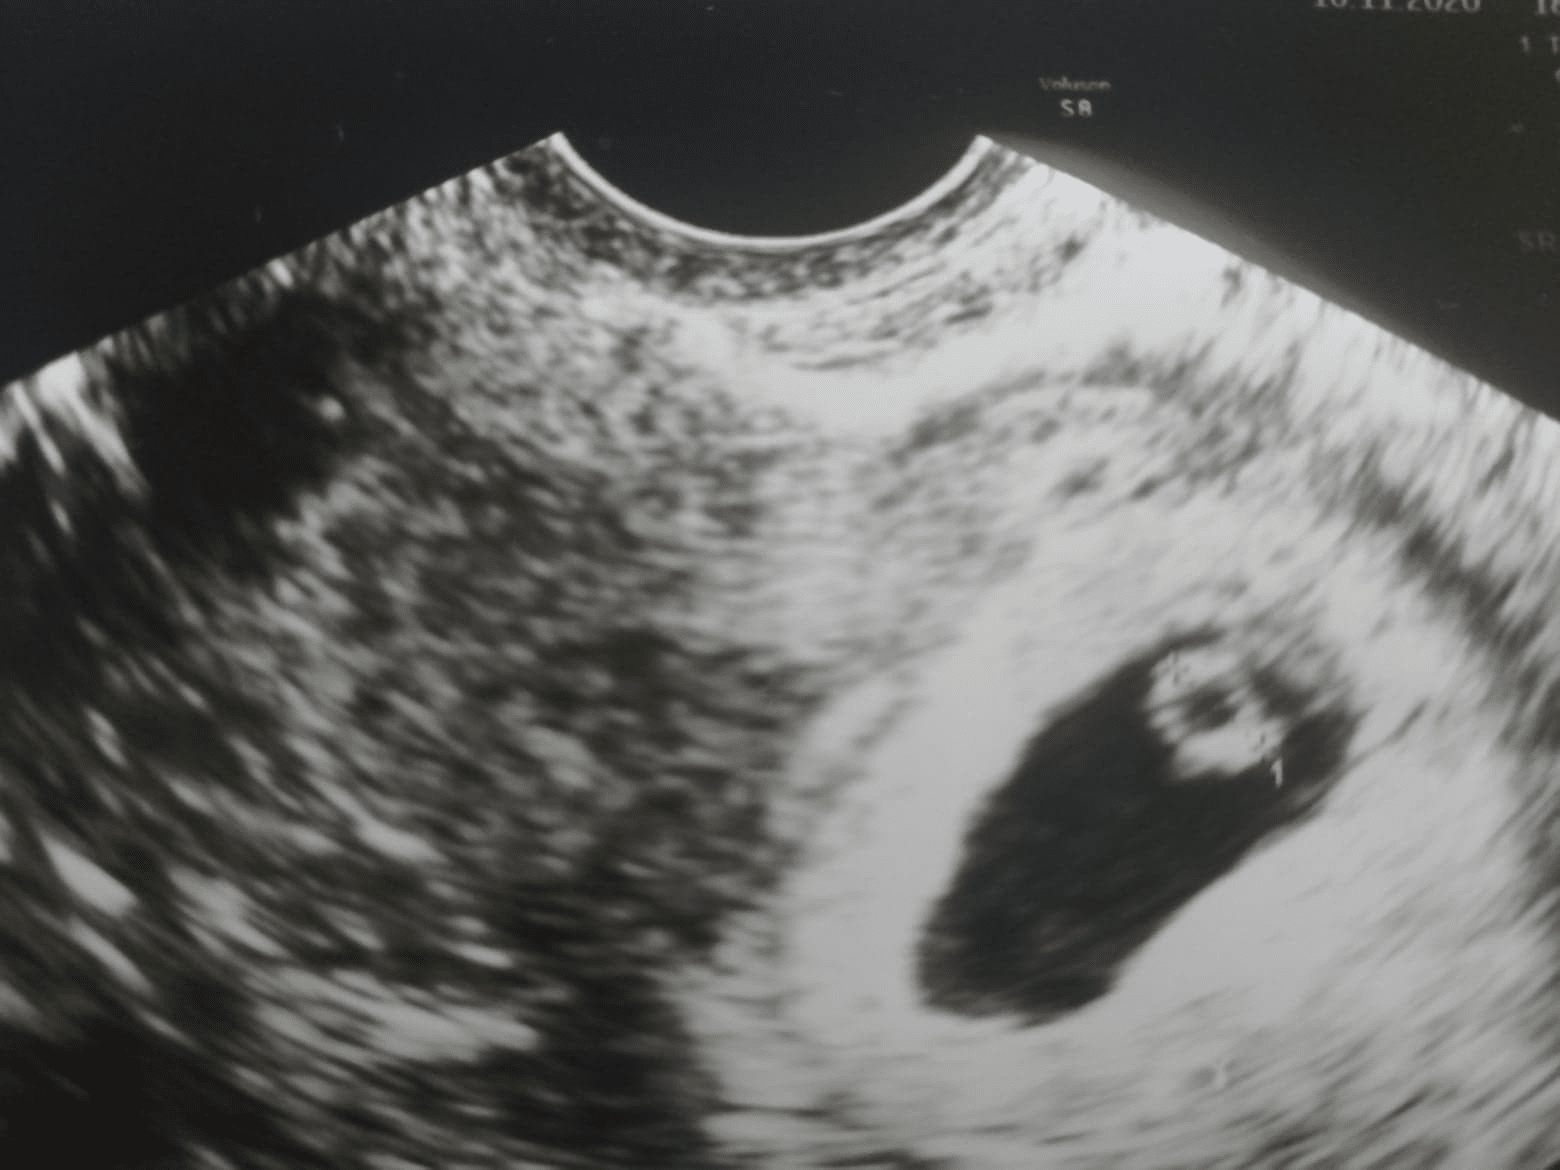

Dodatkowo mam wrażenie, że lekarz i tak wymierzyl ten pecherzyk tak, ze ma mniejszy rozmiar niz na serio, tzn nie od konca do konca tylko troche jakby ucial (czyli ten rozmiar moglby byc jeszcze wiekszy...):

Zobacz załącznik 1200752

Ogólnie też mi się ten kształt wydaje troche nieregularny, a jak widzę zdjęcia z internetu to są piękne, okrągłe pierścienie i mają cieńsze ścianki